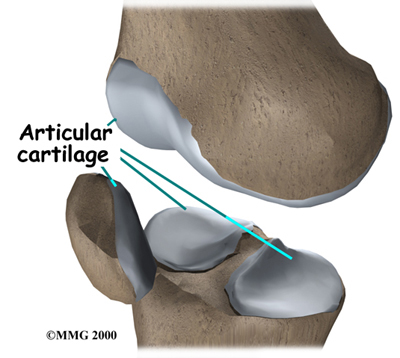

The knee joint is formed where the thighbone (femur) meets the shinbone (tibia). Two bony knobs on the end of the femur, called condyles, sit on the top surface of the tibia. The inside condyle (the one closest to the other knee) is called the medial femoral condyle. The lateral femoral condyle is on the outer half of the femur (farthest from the other knee). The top of the tibia bone forms a flat surface called the tibial plateau.

The knee is divided into two halves, or compartments. The medial compartment is the inside half of the knee and is formed by the connection of the medial femoral condyle and the tibial plateau. The lateral compartment is the outside half of the knee and is formed by the connection of the lateral femoral condyle and the tibial plateau.

covers the ends of bones. It has a smooth, slippery surface that allows the bones of the knee joint to slide over each other without rubbing. This slick surface is designed to minimize pressure and friction as you move.